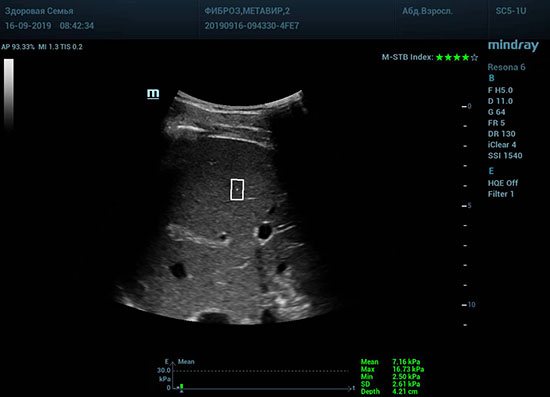

Определение плотности печени. Не ошибся ли оператор при измерении эластических свойств печени? Для оценки критериев качества предусмотрен индекс MBT, который покажет насколько «твердой» была рука оператора и двигалась ли печень. При MBT 5* рука тверда и показатели достоверны. Для оценки качества результатов используется IQR индекс, отображающий колебания показателей в точке измерения при расчете медианы. Показатели при IQR <30% считаются приемлемыми. Техника сканирования через межреберные промежутки требует размещение окна интереса на несколько сантиметром ниже капсулы, для исключения эффекта реверберации. Установка ROI на паренхиму без захвата сосудов, для исключения погрешностей измерения.

Стадия фиброза определяется по системе METAVIR Staging, построенной на данных биопсии и сопоставлении с данными эластографии. Своевременная диагностика фиброза, и начало его лечения, залог благоприятного исхода заболевания.